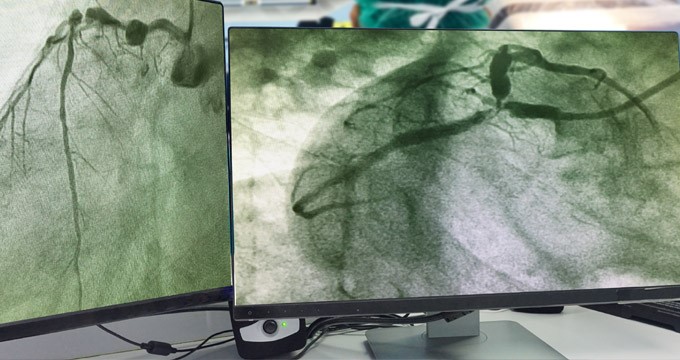

Coronary angiography

You will be awake during this procedure, while your doctor passes a thin, flexible tube (catheter) into a blood vessel via your groin or arm — the area will first be numbed using a local anaesthetic so you won't feel any pain.

Using dynamic X-ray imaging, the catheter will be guided through your blood vessels up into your coronary arteries, which supply your heart. A contrast dye will then be injected through the catheter. As this dye passes through your blood vessels, X-ray images (angiograms) will be taken allowing your doctor to see if any blood vessels are narrowed or blocked.